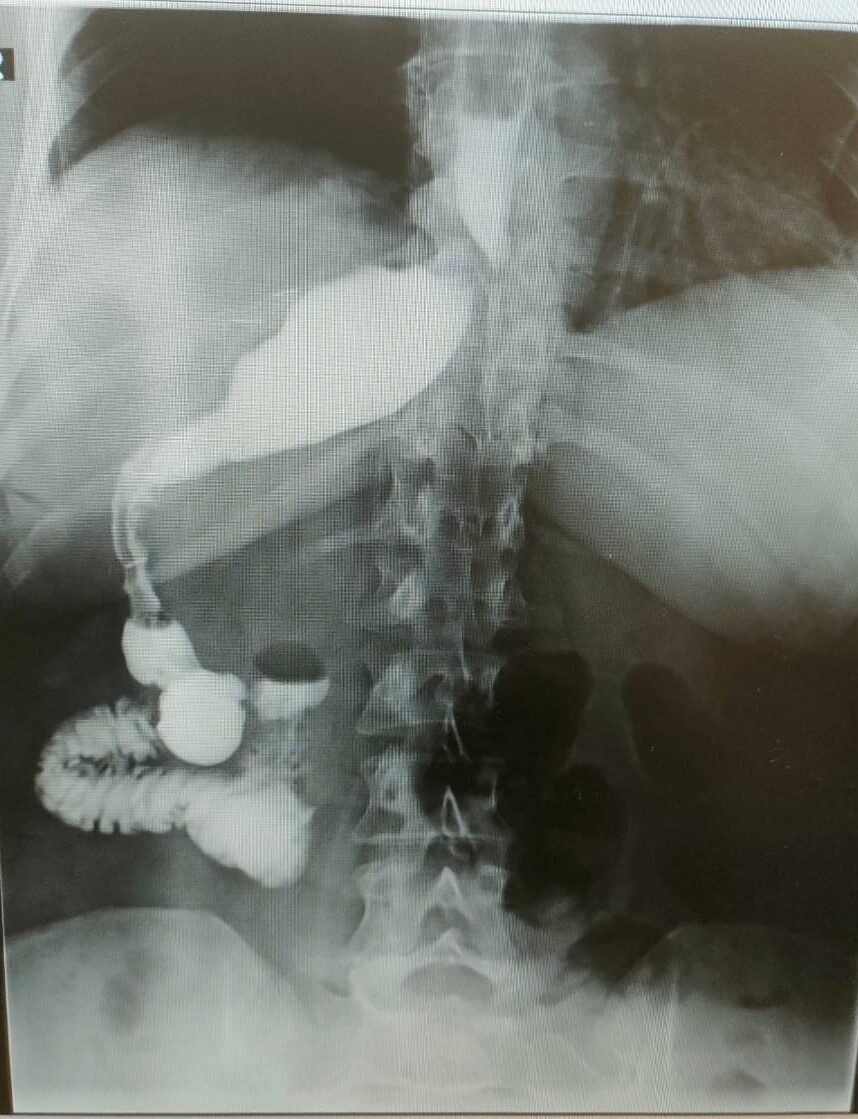

Ameliyatı gerçekleştiren Memorial Antalya Hastanesi Genel Cerrahi Bölüm Başkanı Prof. Dr. Alihan Gürkan, yaşadıkları şaşkınlığı şu sözlerle dile getirdi: “Çok yapılan bu operasyonlar içerisinde hastanın değişik bir anomalisi vardı. 100 binde bir görüldüğü söyleniyor. Organların hepsi ters olabiliyor. Bu daha sık görülen bir şey ama bu hastada bütün organlar yerli yerinde ama sadece mide sağ tarafa kaymış. Yani karaciğerin arkasına gitmiş. Operasyona başladığımızda mideyi bulamadık. Karaciğeri kaldırınca mideyi sağ tarafta gördük. Bu çok nadir bir durum. 2023 yılı verilerine göre, böyle bir tüp mide ameliyatı dünyada yalnızca 50 kişiye uygulanmış. Biz de bu vakayı başarıyla gerçekleştirdik. Teknik açıdan bizi zorlayan ancak deneyimimizi artıran bir ameliyat oldu”.

Prof. Dr. Gürkan, ameliyatın detaylarına değinerek, “Tüp mide operasyonunun ayna görüntüsünü yaptık. Normalde sol tarafta yaptığımız obezite ameliyatını bu hastada sağ tarafta gerçekleştirdik. Midenin karaciğerin arkasında olması ameliyat süresini 15 dakika uzattı ve toplamda 1 saat sürdü. Bizim için de hoş bir tesadüf oldu” diye konuştu.

RÖNTGEN GÖRÜNTÜSÜ